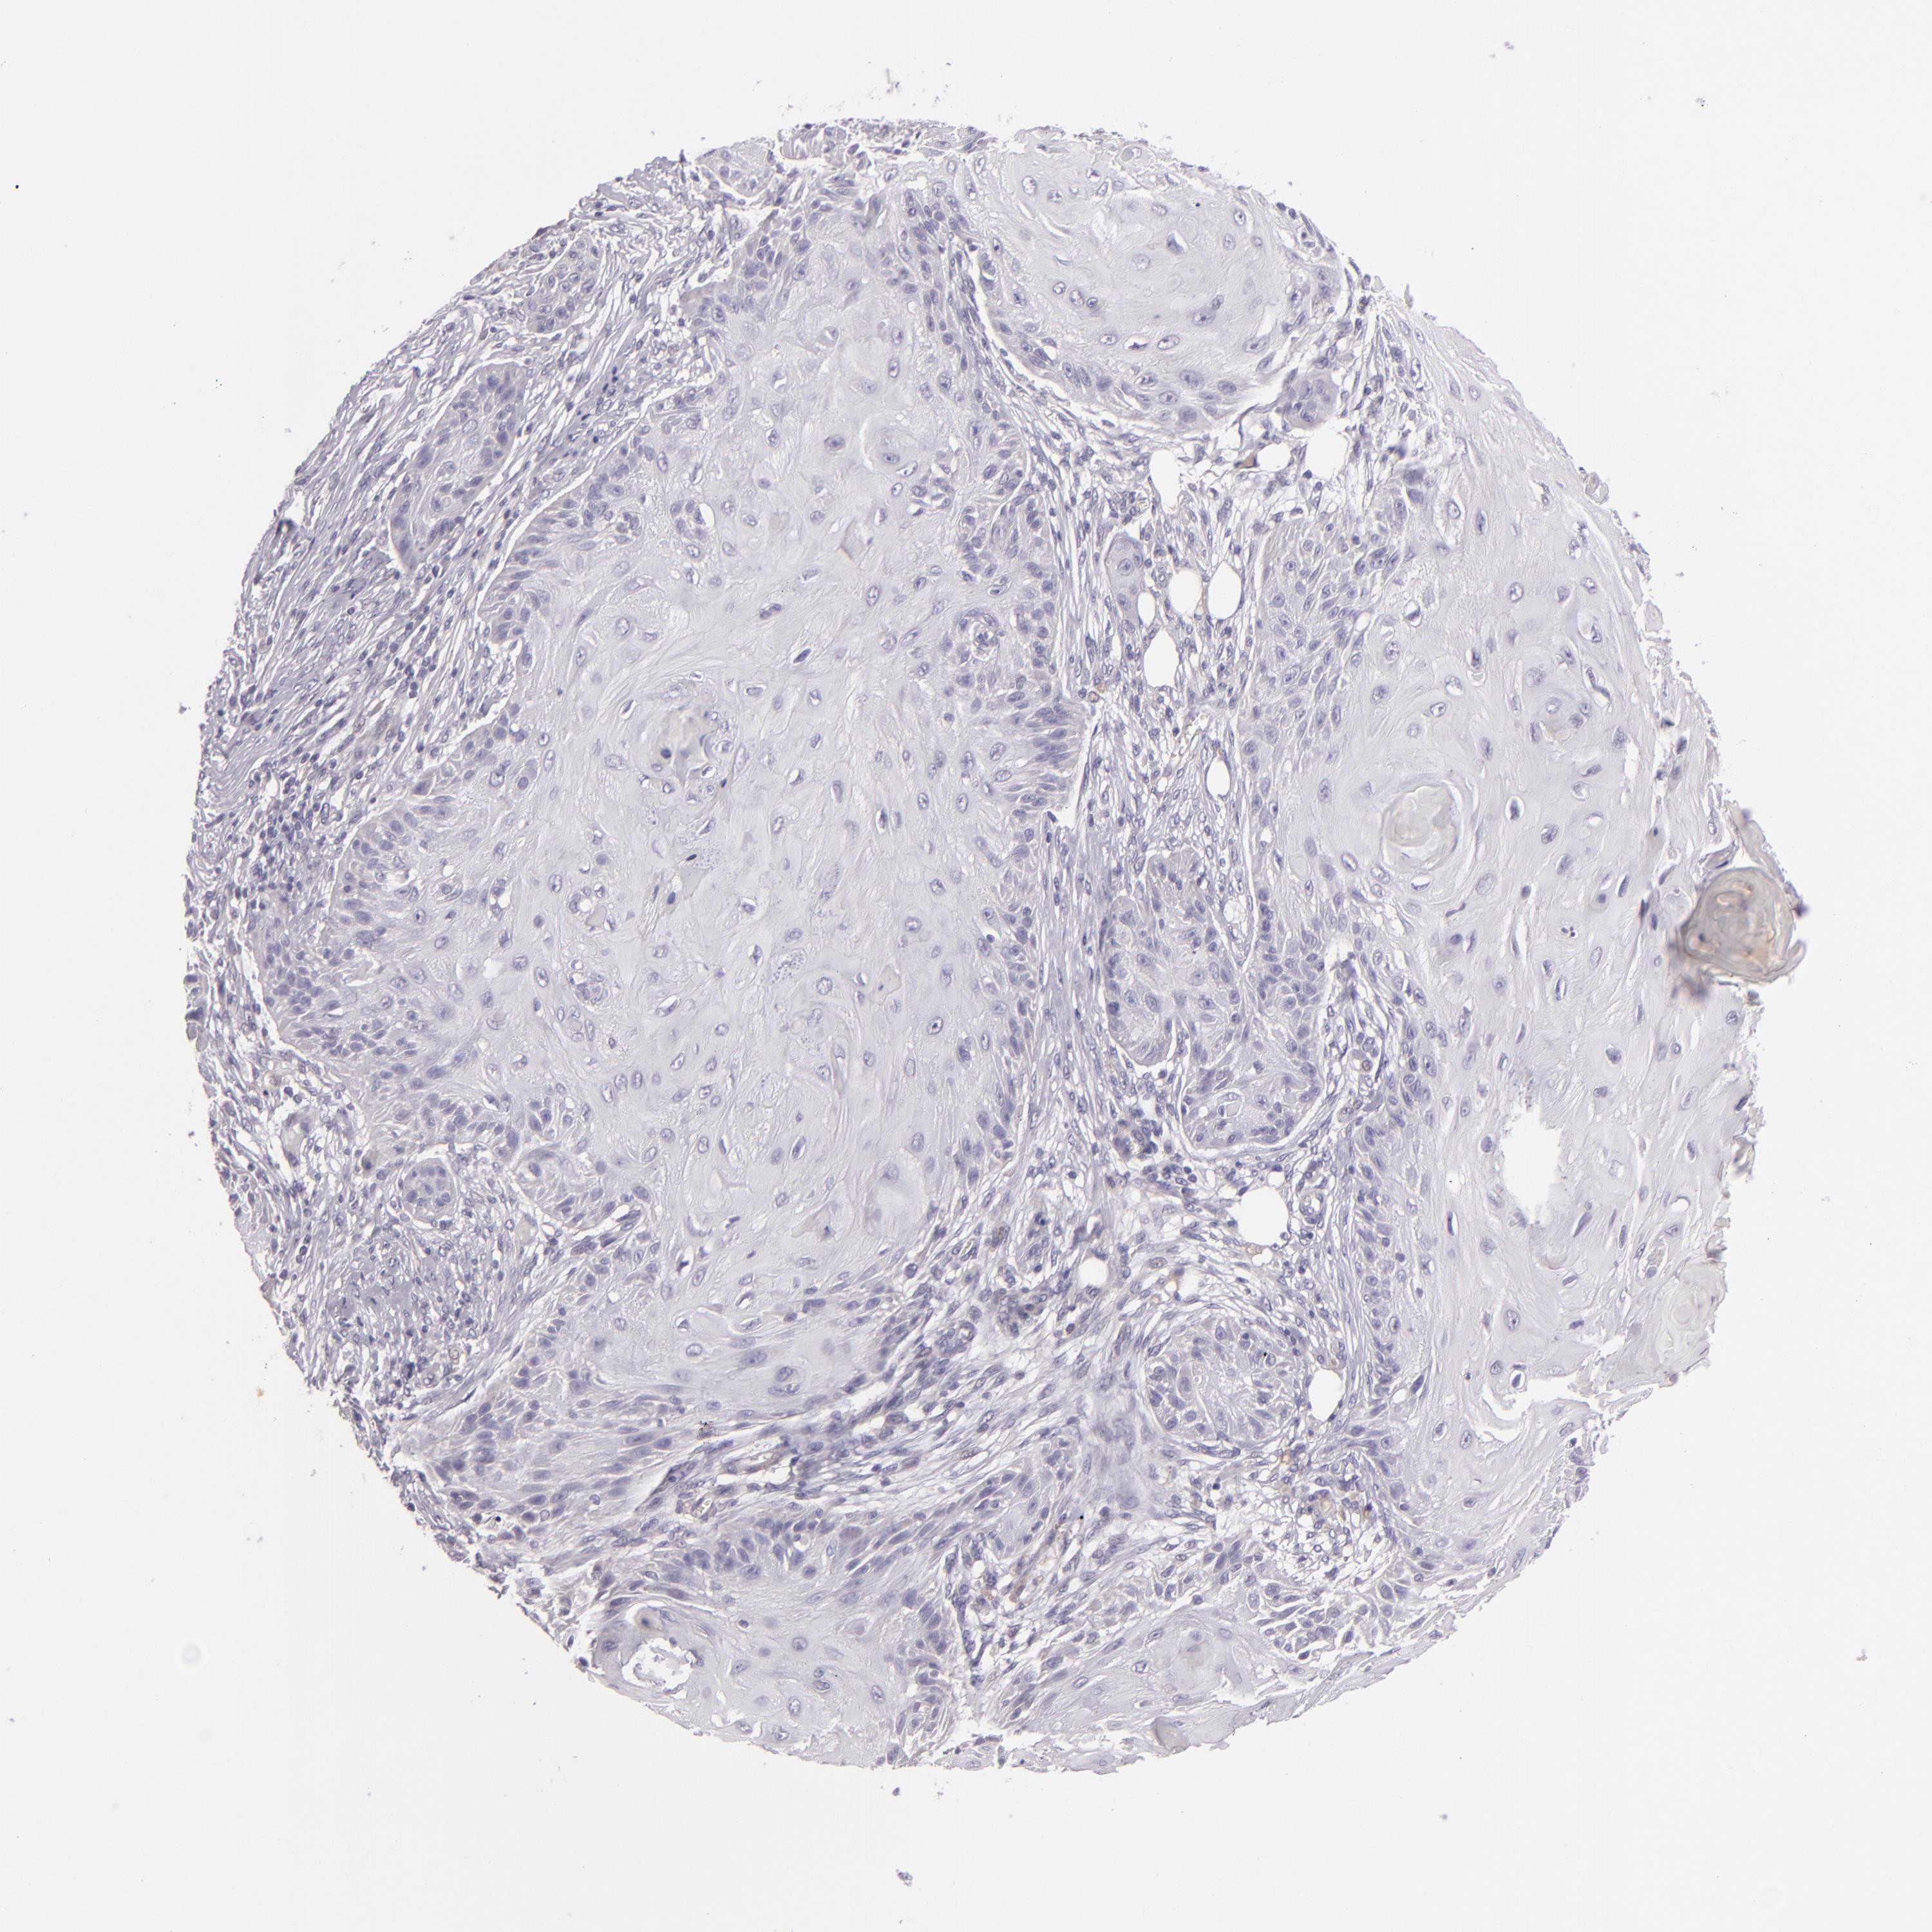

Basal cell and squamous cell cancer

SKIN CANCER - Protein expressioni

A mouse-over function shows sample information and annotation data. Click on an image to view it in a full screen mode. Samples can be filtered based on level of antibody staining by selecting one or several of the following categories: high, medium, low and not detected. The assay and annotation is described here.

Antibody stainingi

Antibody staining in the annotated cell types in the current human tissue is reported as not detected, low, medium, or high, based on conventional immunohistochemistry profiling in selected tissues. This score is based on the combination of the staining intensity and fraction of stained cells.

Each image is clickable and will lead to virtual microscopy that enables deeper exploration of all samples and also displays staining intensity scores, fraction scores and subcellular localization as well as patient and tissue information for each sample.

Antibody HPA001838

Squamous cell carcinoma, NOS

Basal cell carcinoma